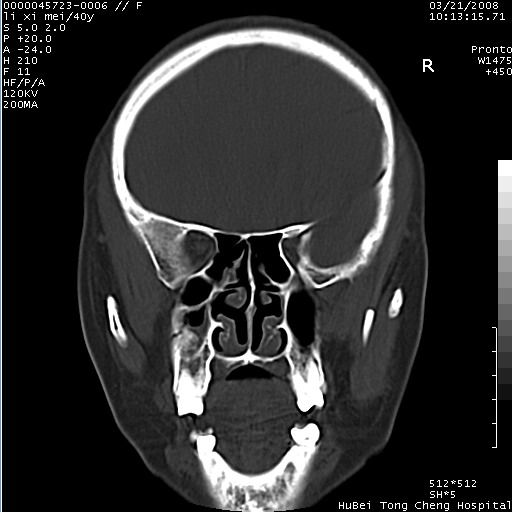

以下是引用卜一在2008-3-21 20:18:00的发言:[br]双侧上颌窦炎症,双下鼻甲肥大!不除外霉菌感染!

以下是引用qiuleiyu在2008-3-21 21:46:00的发言:[br]支持;上颌窦炎,窦内高密度影,建议横断位观察与上颌窦前壁关系。除外骨源性病变。